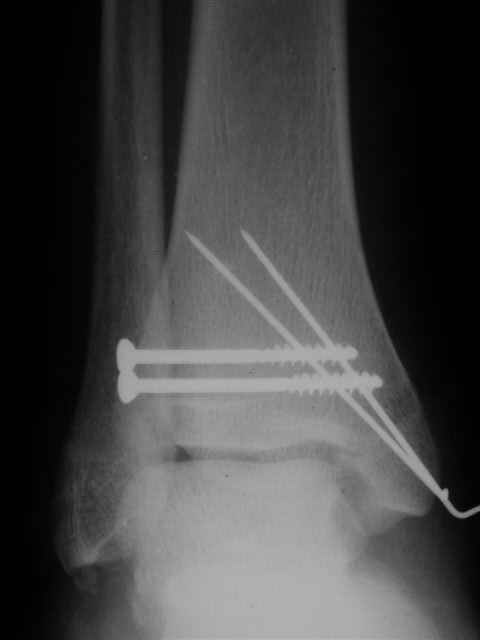

Я предупреждал, что ничего сверхъестественного. Каюсь, что одна из спиц прошла несколько дальше, чем нужно было, но главное - перелом стабилизирован и больной работает суставом в полном объёме, несмотря на представленную раннее травму коленного сустава.

Евгений И Чекашкин